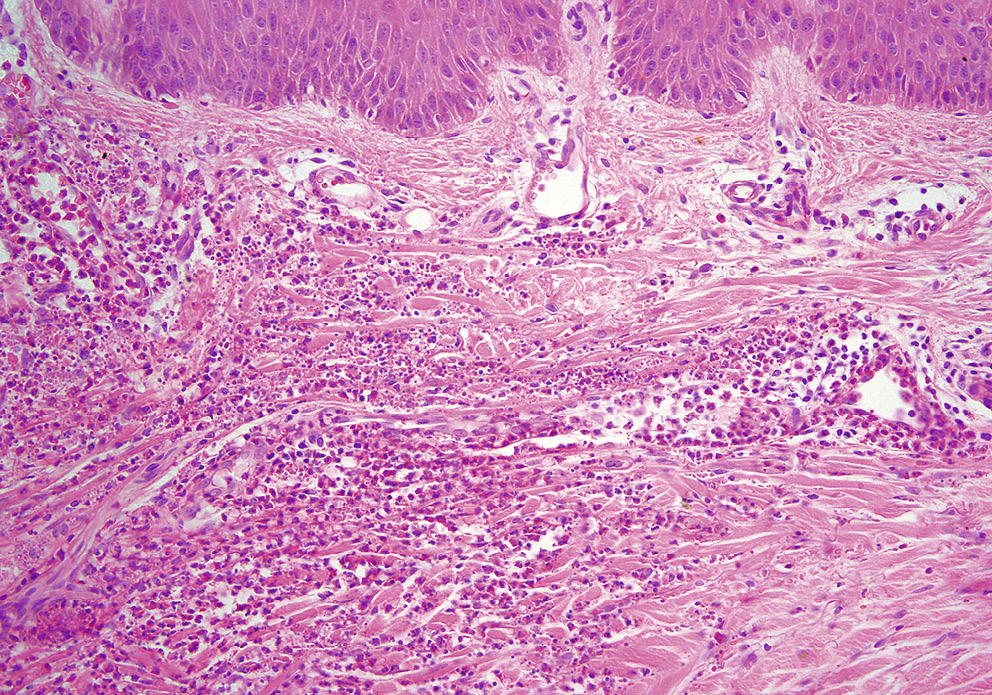

Термин «лейкоцитокластический васкулит» не отражает нозологическую принадлежность сосудистых поражений, является патоморфологическим определением типа (паттерна) повреждения стенки сосудов. Этот морфологический вариант воспаления может наблюдаться при различных васкулитах, отличающихся по механизму развития, а также при вторичных сосудистых поражениях (тканевая реакция по периферии язв, инфицированные повреждения). Для лейкоцитокластического васкулита характерны следующие изменения: наличие нейтрофильных гранулоцитов в стенке и вокруг поверхностных и глубоких сосудов дермы (периваскулярные нейтрофильные инфильтраты, в более старых очагах — смешанные инфильтраты), фрагменты ядер нейтрофилов (ядерная пыль, лейкоцитоклазия), отек, фибриноидный некроз и разрушение стенок сосудов, выход эритроцитов в окружающие ткани (рис. 1, 2) [14, 20].

Рис. 1. Лейкоцитокластический васкулит. Нейтрофильные гранулоциты в стенке и вокруг поверхностных сосудов дермы, фрагменты ядер нейтрофилов (ядерная пыль, лейкоцитоклазия), отек, фибриноидный некроз стенок сосудов

Fig. 1. Leukocytoclastic vasculitis. Neutrophilic granulocytes in the wall and around the dermis' surface vessels, fragments of neutrophil nuclei (nuclear dust, leukocytoclasia), edema, and fibrinoid necrosis of vessel walls

Рис. 2. Лейкоцитокластический васкулит. Выраженный отек сосочковой части дермы. Периваскулярный нейтрофильный инфильтрат с явлениями лейкоцитоклазии

Fig. 2. Leukocytoclastic vasculitis. Severe edema of the papillary dermis. Perivascular neutrophilic infiltrate with leukocytoclasia